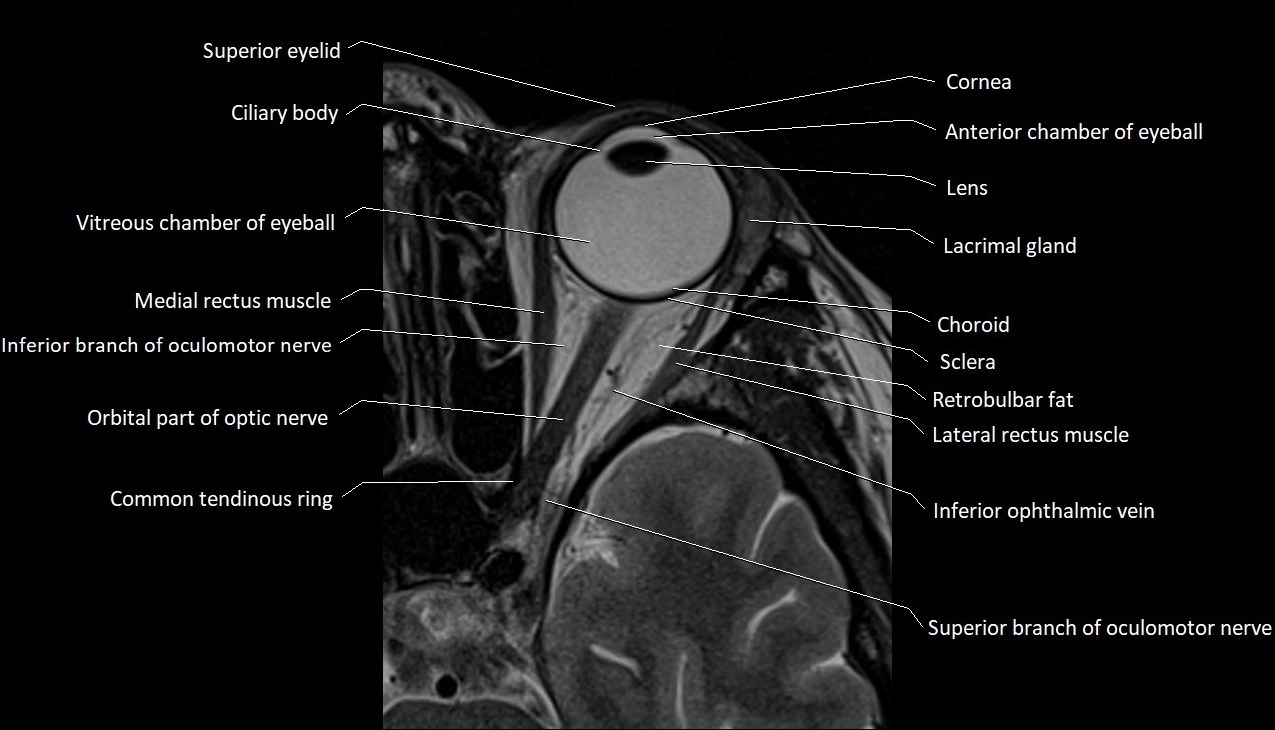

MRI images